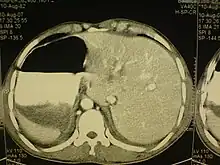

Cet état touche toutes les grandes structures de la cavité thoracique et de l’abdomen. En général, les organes sont simplement transposés par rapport au plan sagittal[1]. Le cœur est situé sur le côté droit du thorax, l’estomac, la rate sur le côté droit de l'abdomen et le foie, ainsi que la vésicule biliaire sur le côté gauche. Le poumon gauche est formé de trois lobes, le poumon droit de deux lobes, tandis que les vaisseaux sanguins, les nerfs, les vaisseaux lymphatiques et les intestins sont également transposés.

Si le cœur est déporté sur le côté droit du thorax, il s’agit d’une anomalie connue sous le nom de situs inversus avec dextrocardie ou situs inversus totalis. Si le cœur reste dans sa position normale, la partie gauche du thorax, il s’agit d’une affection beaucoup plus rare (1 sur 22 000 personnes dans la population générale), désignée par le terme situs inversus avec lévocardie ou situs inversus incompletus. Les personnes atteintes de situs inversus avec lévocardie ou de dextrocardie sans situs inversus présentent des taux beaucoup plus élevés de malformations congénitales que celles qui sont affectées de situs inversus avec dextrocardie. De plus, les individus atteint de cette malformation avec une lévocardie sont des cas qui s'accompagnent souvent de troubles cardiaques[1].